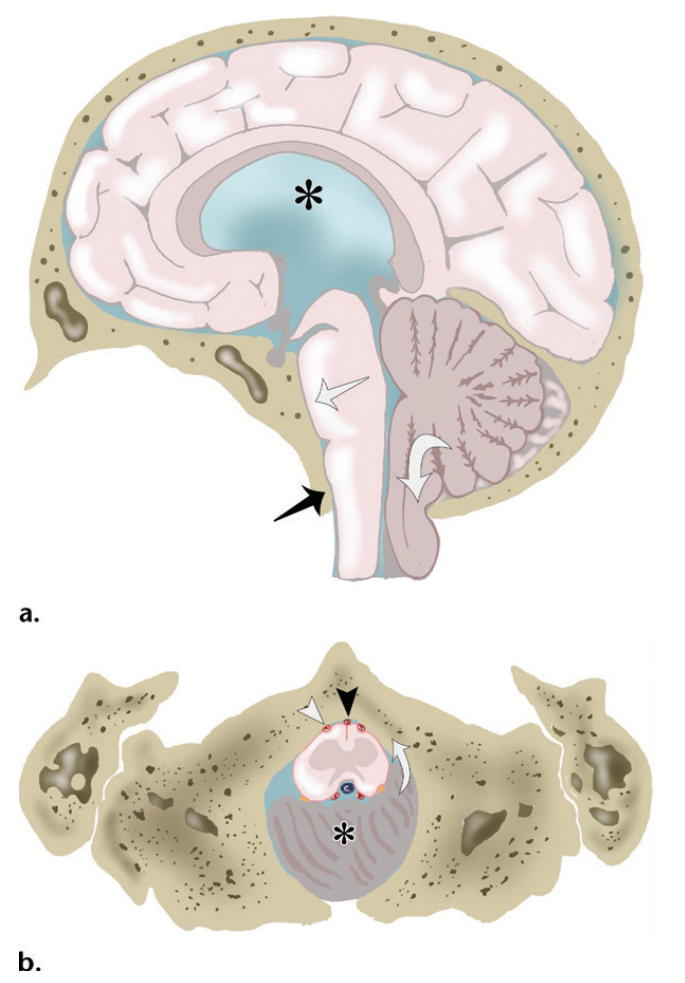

②枕骨大孔疝(transforamen magna herniation),为小脑扁桃体及延髓经

当小脑扁桃体疝入枕骨大孔时,阻塞了脑嵴液的循环,并且可能压迫脑干和

(a图)小脑扁桃体延伸至枕骨大孔的下方(白色弯曲箭头),脑干挤压斜坡

当小脑扁桃体向下疝出超过枕骨大孔下缘5mm即可诊断为小脑扁桃体下疝

枕骨大孔疝可以压迫脑干的生命中枢,直接引起患者的死亡,情况非常危及